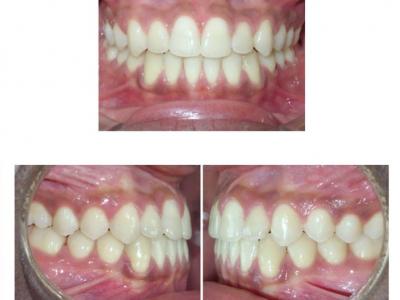

Les deux patients sont classe III squelettique (léger) avec un articulé inversé antérieur, mais avec des rapports de classe I molaire et des diastèmes.

Des dispositifs multi-attaches linguaux ont été choisis pour des raisons esthétiques et pour avoir des torques individualisés.

La principale astuce a été de placer des mini-vis vestibulaires (impossibles en lingual à cause de l'inconfort et de la perte de celles-ci avec les contraintes linguales), de tendre une chaînette entre ces mini-vis en vestibulaire et de bloquer l'élément élastomérique par un point de composite sur les incisives centrales inférieures. L'intérêt est de ne pas avoir recours à des élastiques inter-arcades et donc de ne pas compenser le haut (version inesthétique des incisives supérieures), de ne pas basculer les plans d'occlusion et de ne pas solliciter la coopération des patients. Ceci nous a aussi dispensé de chaînettes linguales, sources d'accumulation bactérienne.

Le recul des incisives inférieures a permis la correction de l'articulé inversé et repositionné les lèvres (gain esthétique). Les torques ont été bien contrôlés avec des systèmes différents (le premier avec une insertion verticale de l'arc au niveau antérieur et le deuxième avec une insertion horizontale). Le contrôle du torque ne dépend donc pas du type d'insertion, mais du niveau d'insertion de l'arc dans les attaches (insertion au fond pour contrôler) et du jeu de l'arc dans ces dernières.

Dans le premier cas, une autre astuce a été de ne pas coller les attaches en lingual sur les 7 et de placer des sectionnels en vestibulaire sur les 6 et les 7 (gorges 022x028). L'intérêt est de ne pas avoir un arc en lingual dépassant lors du recul (et donc blessant), et d'augmenter le glissement au niveau des molaires en utilisant des gorges plus larges.